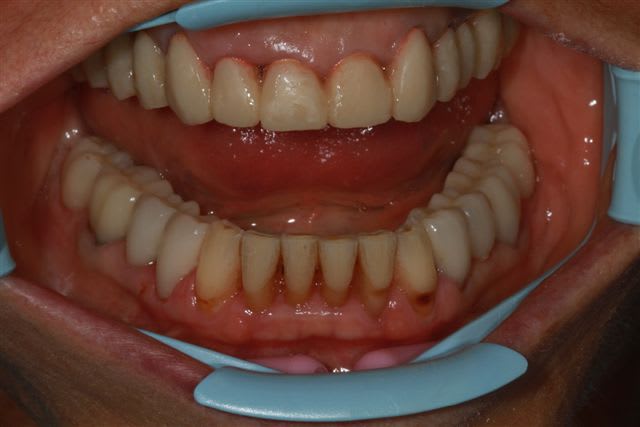

Ce matin pose de 8 ceramoceram (emax press) à la mandibule et pano de contrôle.

Je crois de plus en plus qu'extraire pour faire une MCI n'était pas le bon choix.

screws post titane (anthogyr sous réserves)scellés.

Bridge provisoire "maison" d'après Wax up mais résine cuite au four sous pression d'azote (Kerr)

Emax traitement acide, puis silane Kerr (avec résine) et collé au NX3

Nettoyage soigneux des excès et radio de contrôle puis polissage doux.

équilibration en fin de séance et contrôle 3 h après.